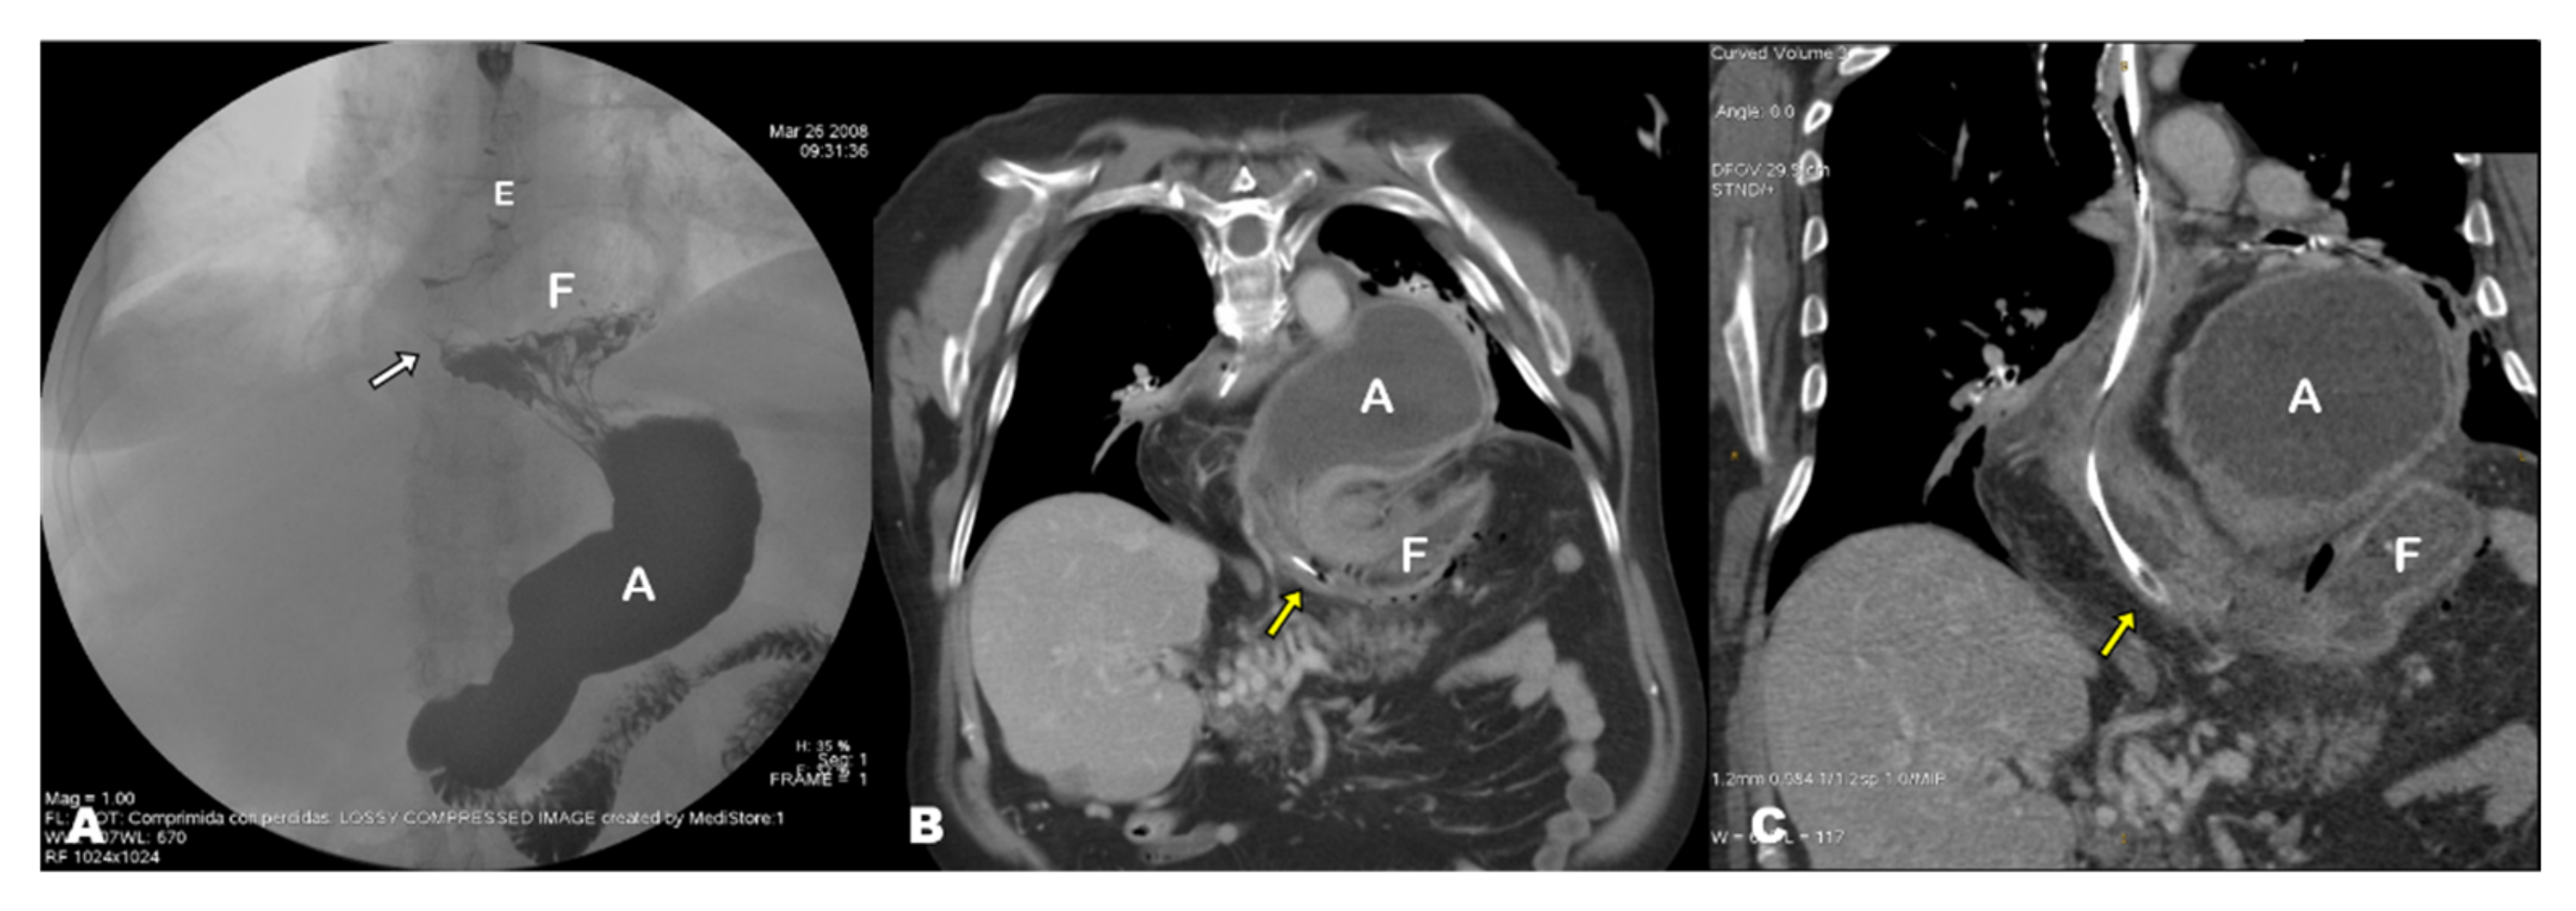

3. Results